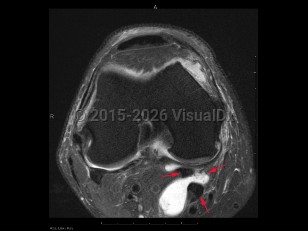

Imaging Studies image of Popliteal cyst - imageId=7921070. Click to open in gallery.  caption: '<span>Axial intermediate fat  saturated MRI sequence demonstrates a popliteal cyst (Baker's cyst), with  fluid tracking between the medial head of the gastrocnemius and  semimembranosus tendons.</span>'

Axial intermediate fat saturated MRI sequence demonstrates a popliteal cyst (Baker's cyst), with fluid tracking between the medial head of the gastrocnemius and semimembranosus tendons.